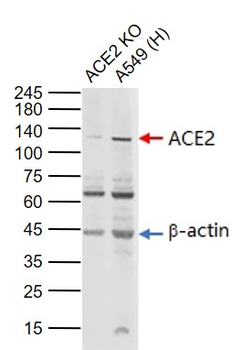

WB

Human

Mouse, Rat

Rabbit

Polyclonal

Unconjugated

50 μl, 100 μl, 200 μl - Featured